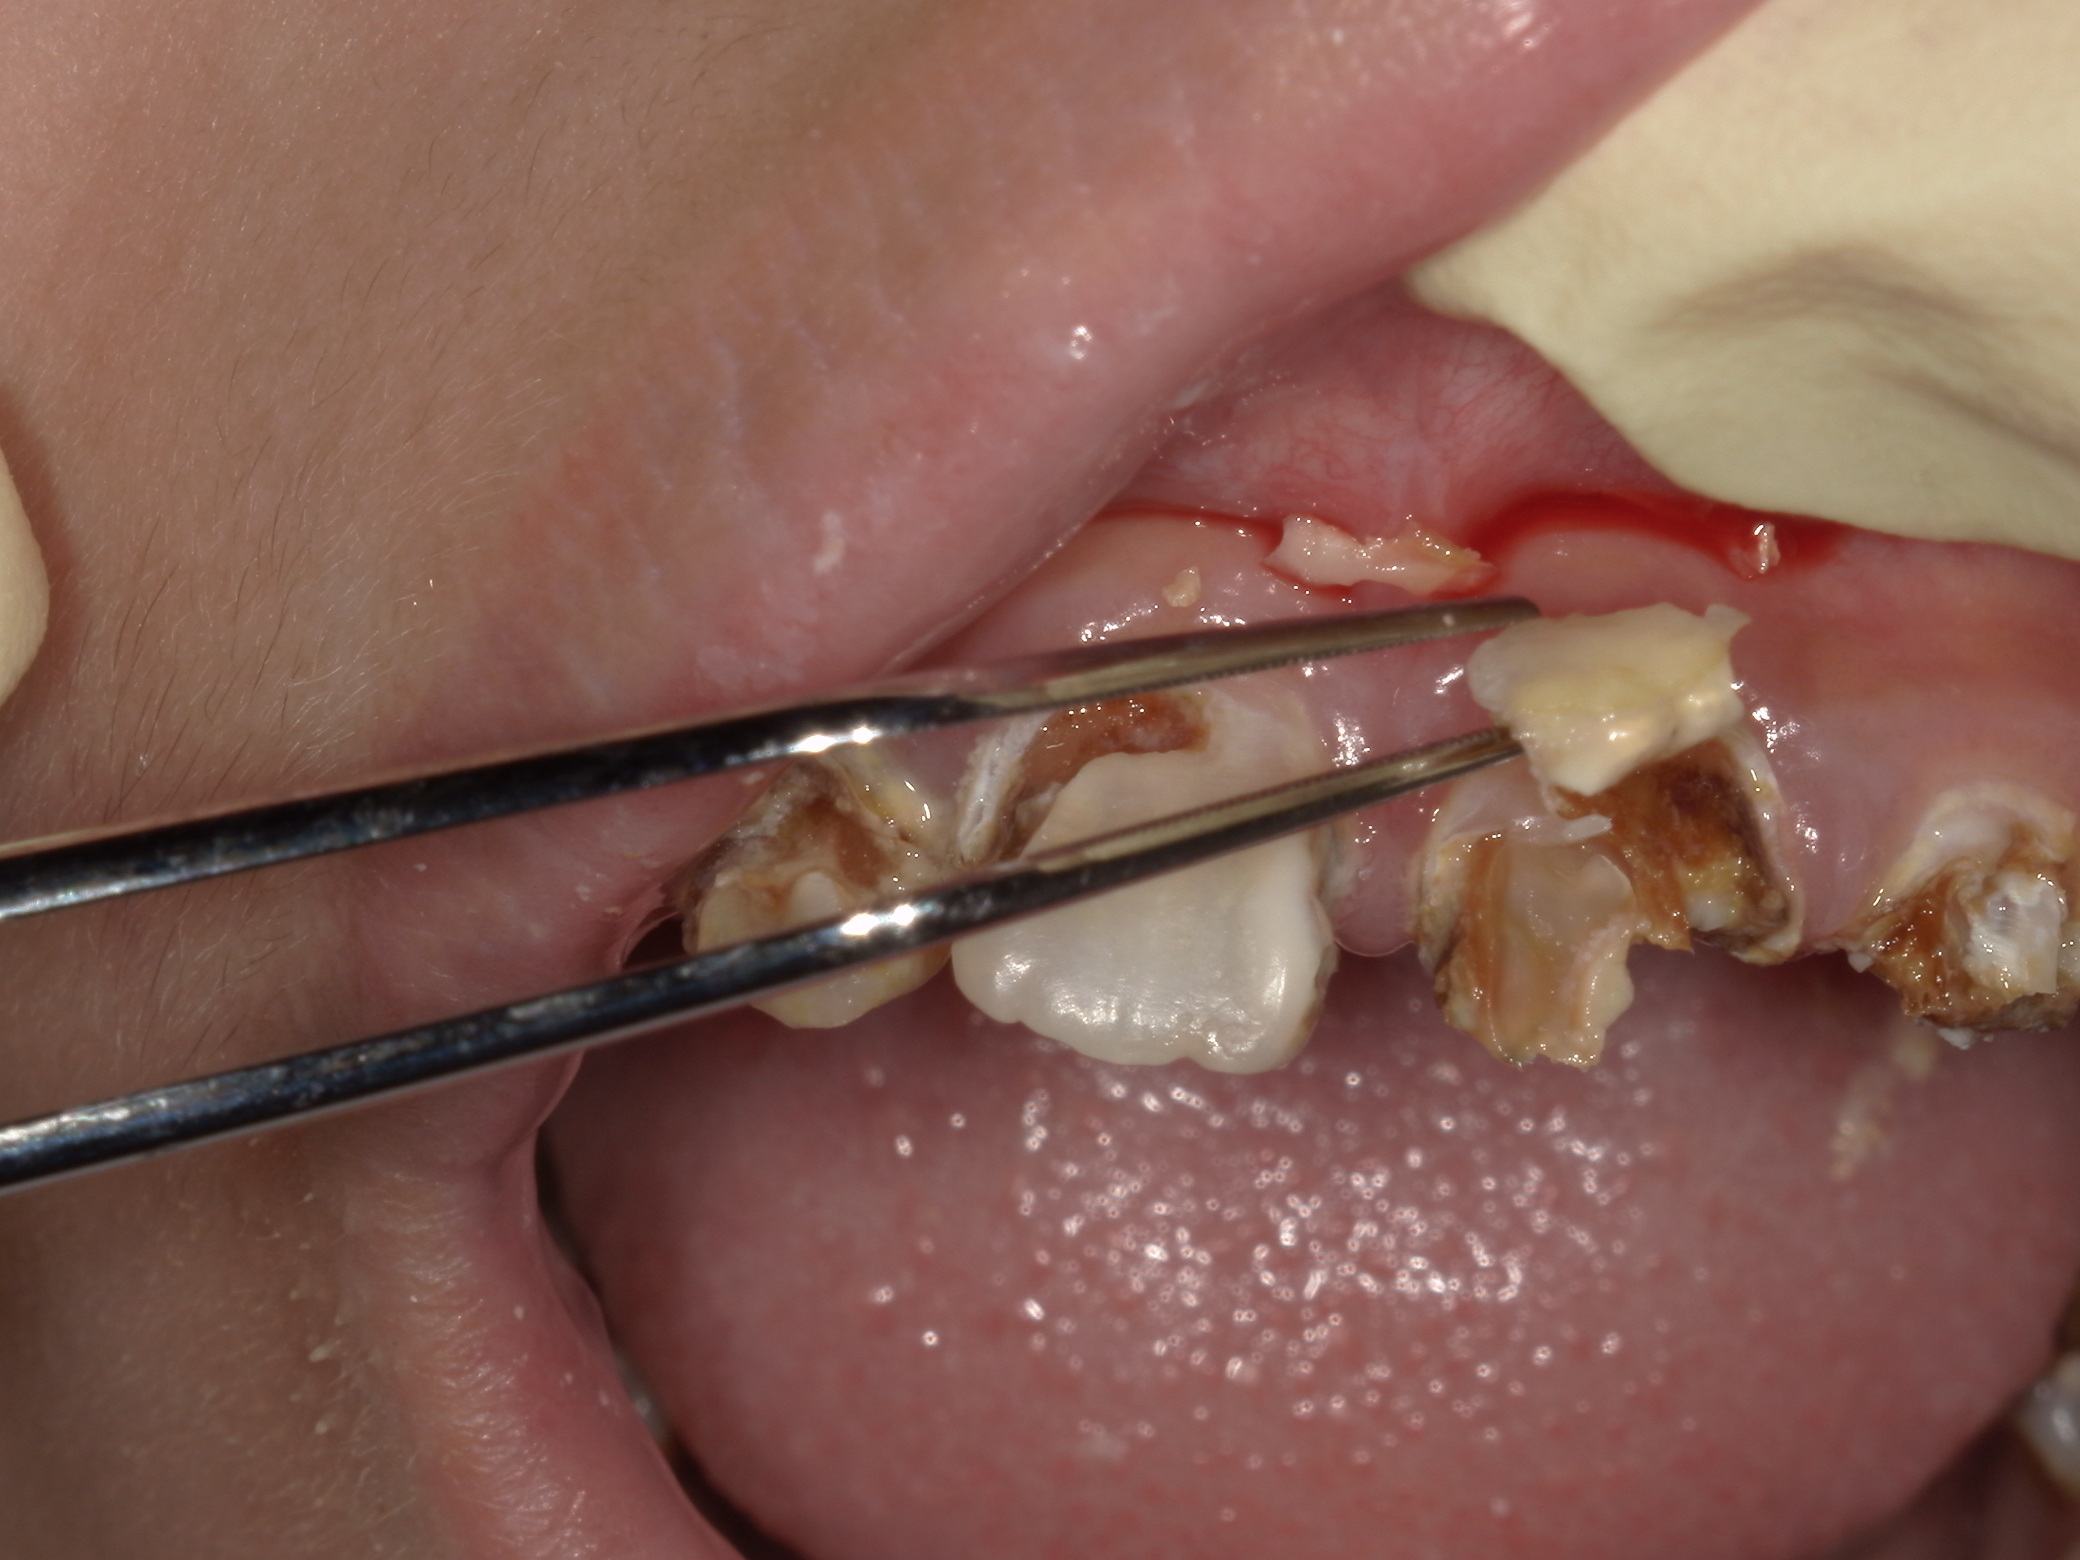

ドックベストセメント治療の問題点

先日3例目のドックベストセメント治療を受けた酸蝕歯の患者さんが何回通院しても治らないということ...

ドックベストセメント治療の失敗

先日2例目のドックベストセメント治療でトラブルになった患者さんが来院された。 写真の右下7番は...

ドックベストセメント治療の被害

最近、ドックベストセメントによる治療のトラブル例が増えています。 写真はドッグベストセメント治...